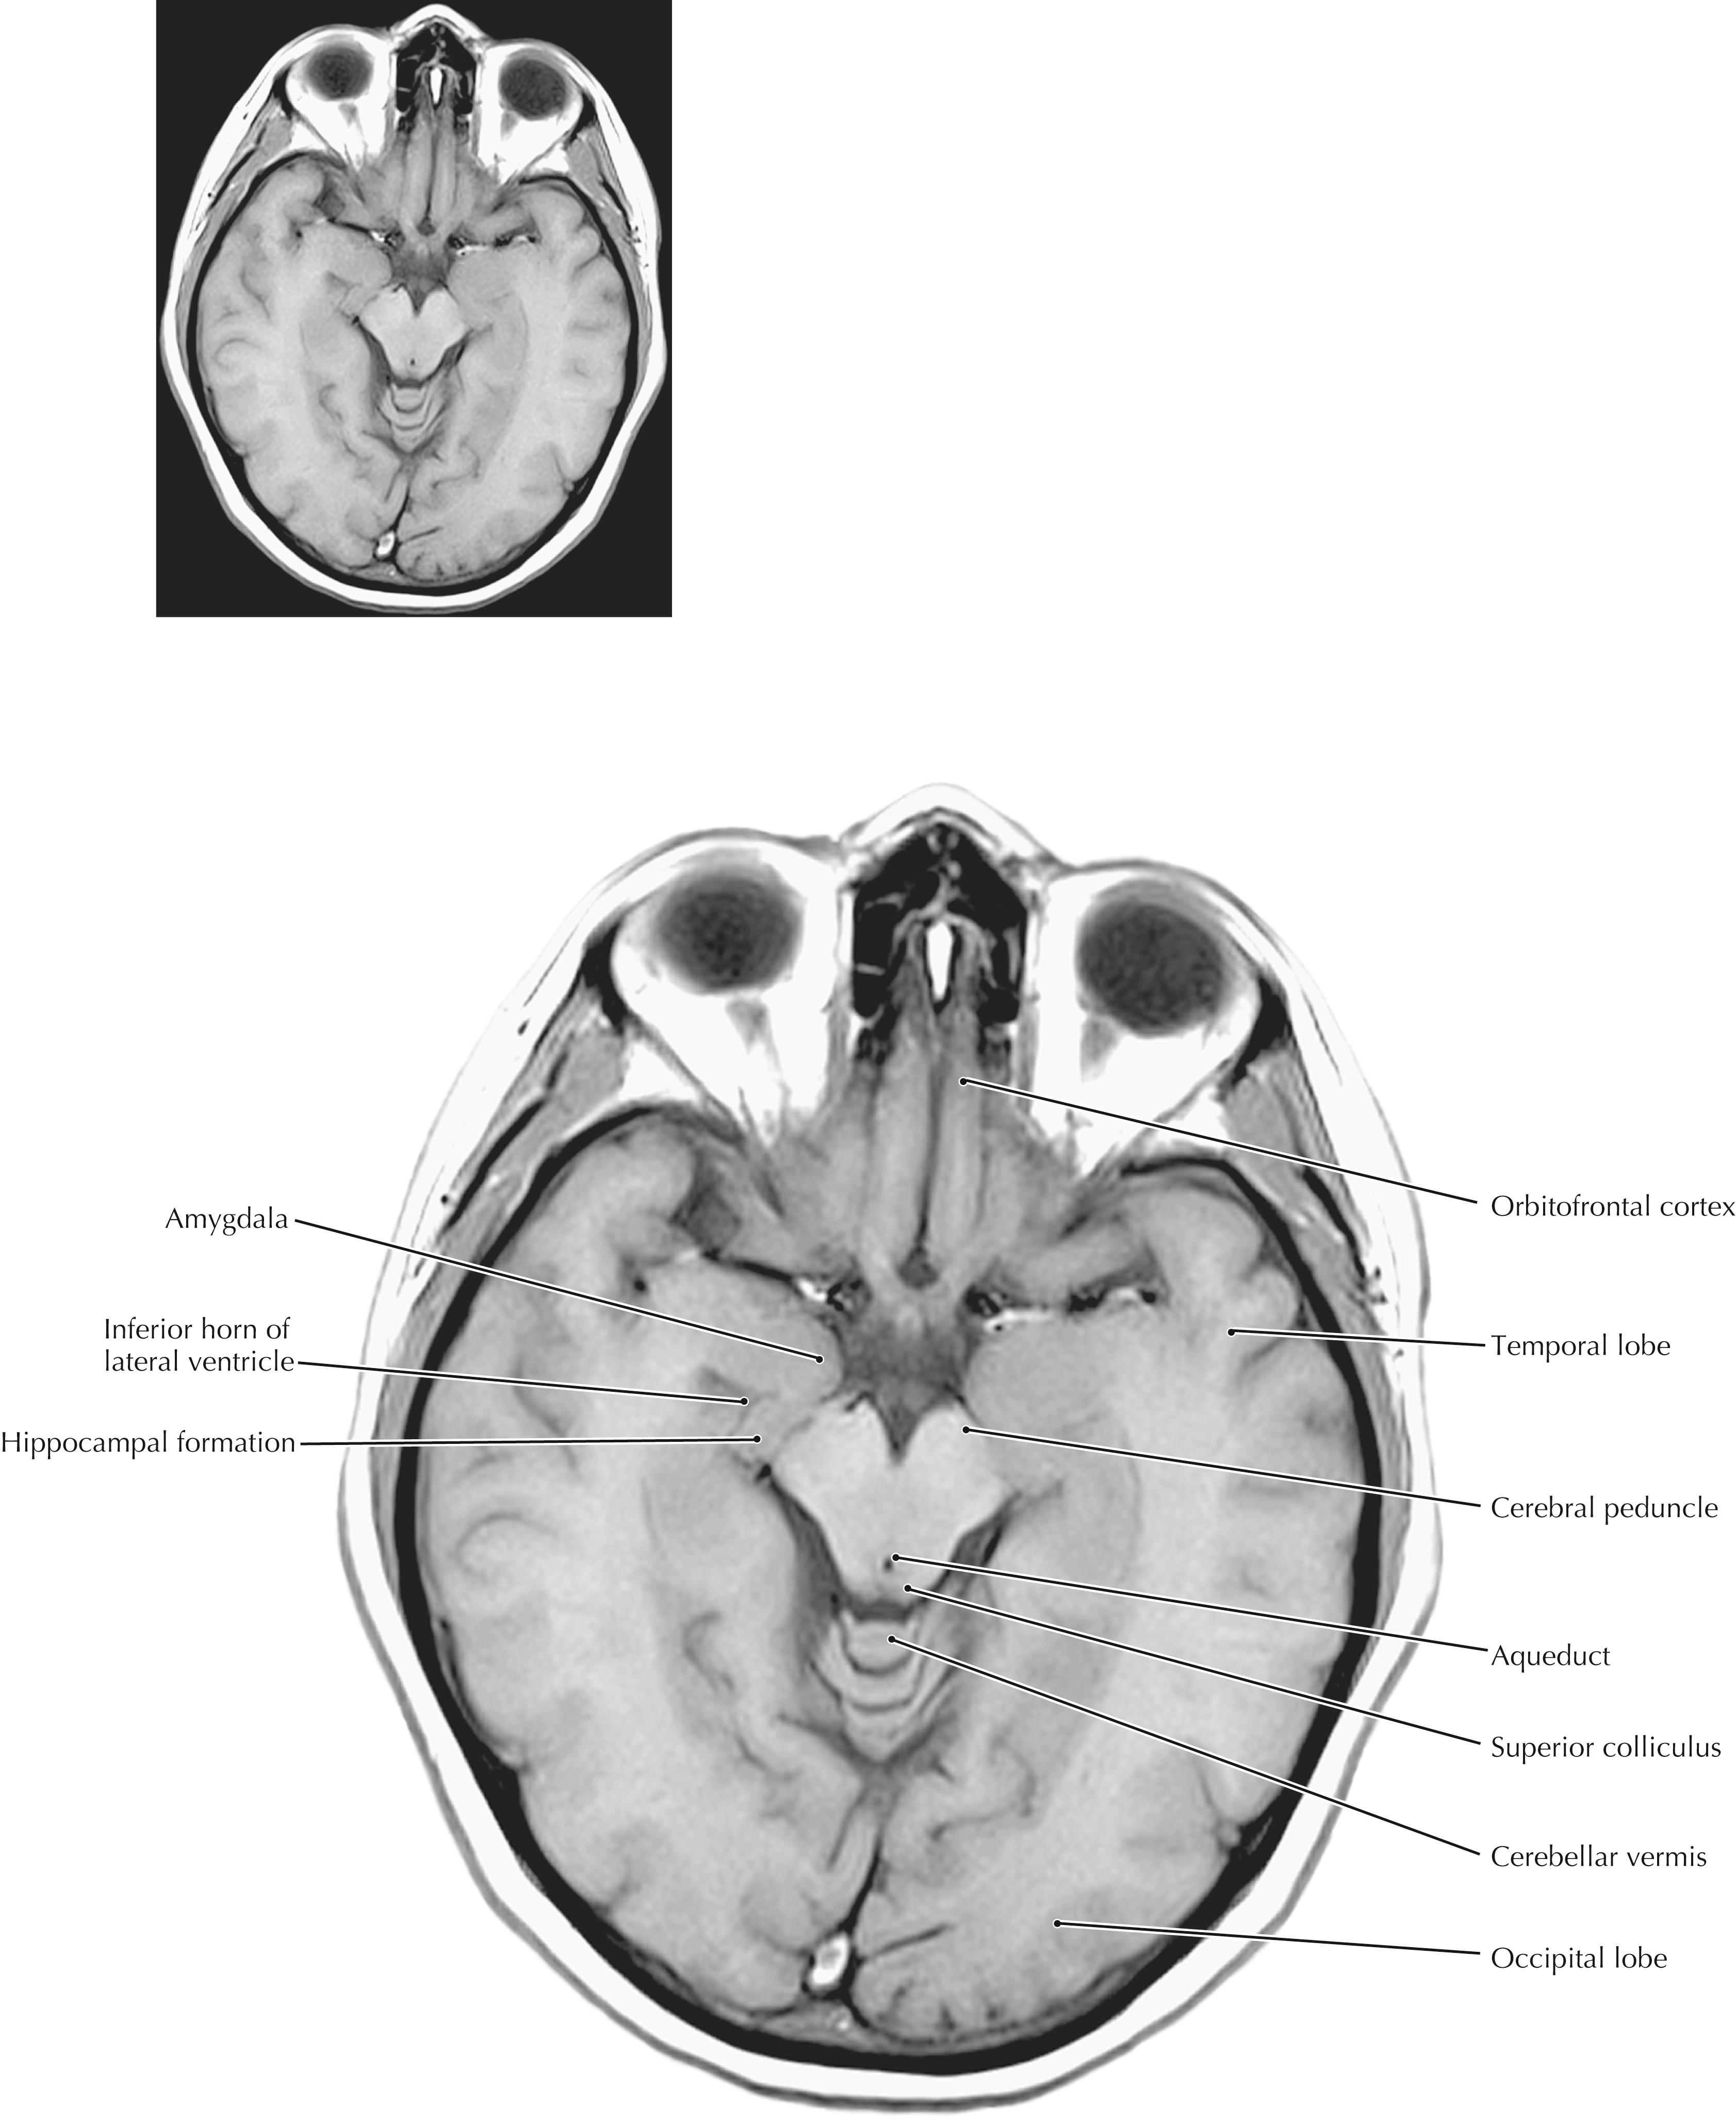

These axial (horizontal) sections compare anatomical sections and high-resolution magnetic resonance (MR) images. They are cut in the true horizontal (axial) plane, not in the older 25-degree tilt. The most important anatomical relationships in these sections center on the internal capsule (IC). The head of the caudate nucleus is medial to the anterior limb of the IC and forms the lateral margin of the frontal pole of the lateral ventricle. The thalamus is medial to the posterior limb of the IC. The globus pallidus and putamen are lateral to the wedge-shaped IC. The posterior limb of the IC carries the major descending corticospinal, corticorubral, and corticoreticular fibers and the ascending sensory fibers of the somatosensory and trigeminal systems. The most posterior portions of the posterior limb also carry the auditory and visual projections to their respective cortices. The genu of the IC carries the corticobulbar fibers. The anterior limb of the IC carries cortical projections to the striatum and the pontine nuclei (pontocerebellar system). The full-plate MR images are T1-weighted; the ventricles appear dark. The scout MR images that accompany the drawings are T2-weighted MR images, in which the cerebrospinal fluid (CSF) appears white.

The temporal lobe includes the amygdaloid nuclei, the hippocampal formation and associated cortex, the transverse gyrus of Heschl, some language-associated cortical regions (Wernicke’s area in the dominant hemisphere), Meyer’s loop of geniculocalcarine axons, the inferior horn of the lateral ventricle, and extensive cortical areas (superior, middle, and inferior temporal gyri). The temporal lobe can be damaged by trauma, infarcts, tumors, abscesses, and other pathological conditions. Such damage can result in auditory hallucinations, delirium and psychotic behavior, sometimes a contralateral upper quadrantanopia (if Meyer’s loop is damaged), and receptive aphasia (Wernicke’s aphasia) that involves a lack of understanding of verbal information (in a lesion of the dominant hemisphere). Some very specific lesions in the temporal lobe result in an agnosia for recognition of faces (prosopagnosia).

Axial (Horizontal) Sections Through the Forebrain: Level 3—Midbrain